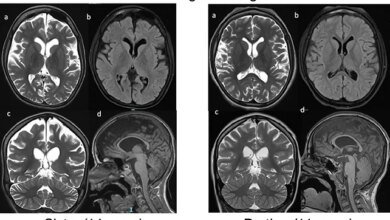

متلازمة ReNU2: جين صامت يكشف اضطرابًا عصبيًا جديدًا يضرب الآلاف

آلاف الأطفال حول العالم يواجهون تشخيصًا جديدًا. متلازمة ReNU2، اضطراب عصبي نمائي وراثي، أخيرًا كُشف عنها. هذا المرض، الذي يمثل…